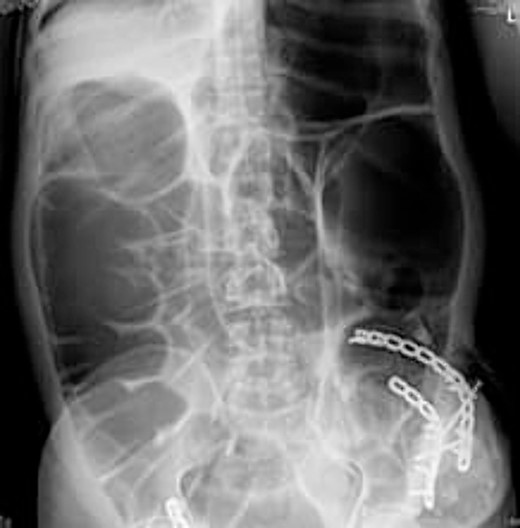

Radio imaging was requested for the patient at admission. Erect X.R. has been taken, showing dilated bowel loops (Figs 3 and 4).

The CT abdomen pelvis (Figs 5 and 6) showed signs of bowel obstruction signs, along with an internal hernia at the place of the prior ORIF surgery. These findings were thought to be the core cause of the patient’s presentation in align with the taken history, physical examination of the patient.

The preferred imaging method is computed tomography. While ultrasound is a low-cost, low-risk alternative for assessing these hernias, it does not reveal concomitant abdominal illness and is used less frequently in clinical settings [22, 23]. Conventional X-rays revealed dilated bowel segments. The computed tomography (CT) picture indicated several dilated colonic segments as well as a hernial defect on the left side of the abdomen. Moreover, ultrasonography of the abdomen and pelvis revealed a moderate reactive free fluid accumulation in the pelvis and a bowel loop imprisoned in the apparent bulge.